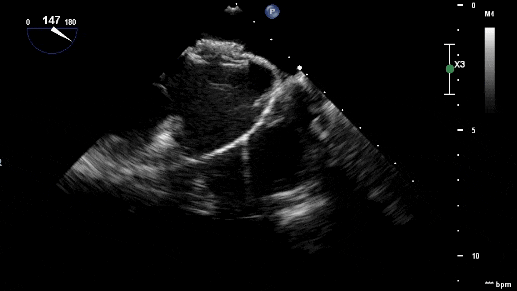

沿加硬導絲將9F輸送鞘送至左心房,退出導絲及輸送鞘內芯后,在超聲引導下送入1824PFO封堵器進行封堵。先釋放左盤面,整體回撤,緊貼房間隔,后釋放右盤面,進行推拉試驗,超聲在主動脈短軸切面、四腔心切面確認封堵器對二尖瓣等周圍組織無影響,位置及形態良好后釋放封堵器。撤出長鞘、縫合穿刺點后壓迫止血,加壓繃帶包扎,手術結束。

超聲觀察對周圍組織無影響

封堵器釋放后成型良好,無殘余分流